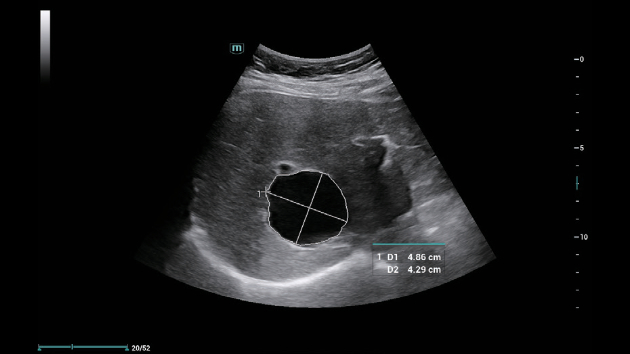

ZST+ ??? ???? ?? ???

ZST+ ???? ???? ??? ???? ??? ?????. ??? ???? ?? ? ???? ?? ??? ?? ??? ?????. ??? ??? ? ?? ??? ??? ???? ?????? ??? ???? ???? ??? ?? ?? ?? ?? ???? ?? ??? ?? ??? ?????.